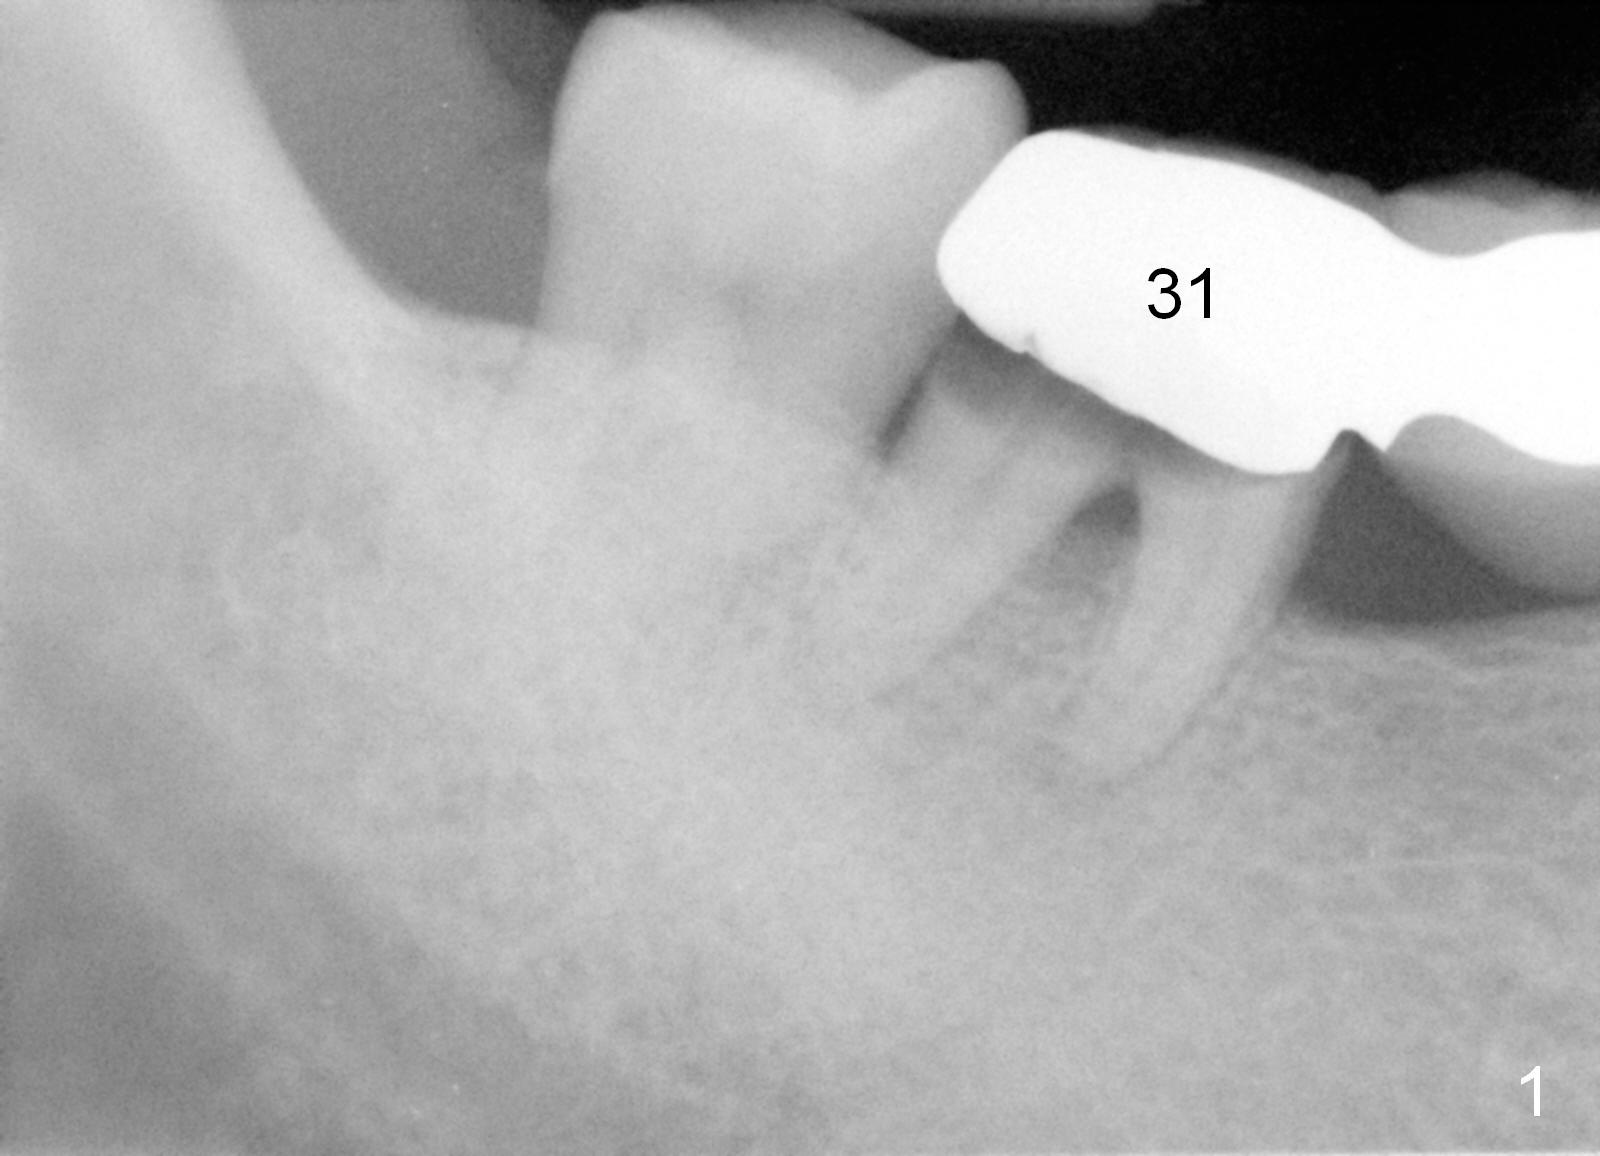

A 47-year-old man works in Africa. While he is visiting his family at Atlanta, he has toothache in the lower right. Examination reveals secondary caries under #31 retainer (Fig.1) and mesial open margin of #28 retainer (Fig.2). Surgery is scheduled next day.

Before sectioning between #29 and 30 (Fig.4 dashed line), take Alginate impression for the lower right quadrant to fabricate a surgical stent. Two implants are to be placed at the sites of #30 (5x14 mm) and 31 (6x14 mm) (Fig.3,4).